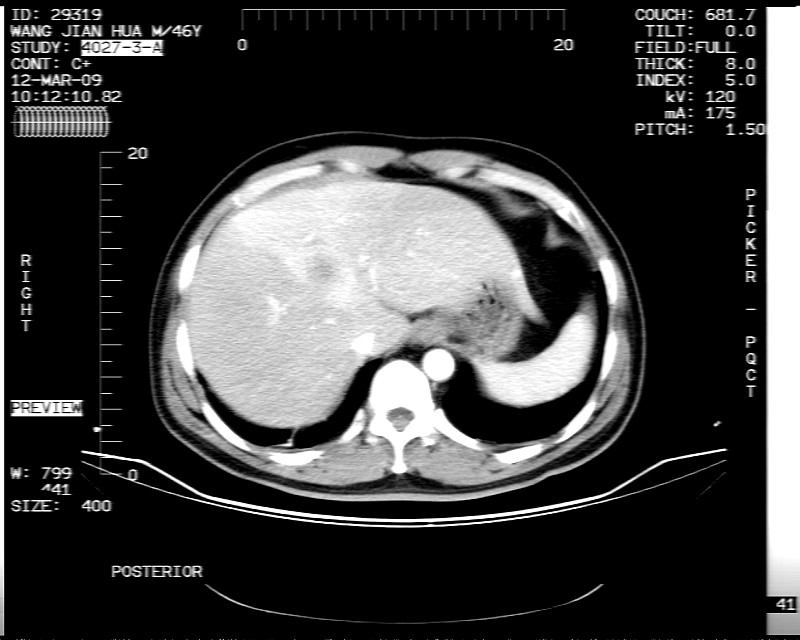

男性,52岁,腹痛,无发热,生化检查无明显异常,既往有胰腺炎病史,经治疗好转出院。

胆囊炎,肝脓肿(周围可见异常灌注)

1)考虑肝左叶内侧段肝脓肿,不排除转移瘤。2)脂肪肝。3)慢性胆囊炎。4)十二指肠降部肿瘤可能。

胆囊炎、脂肪肝、肝脓肿。